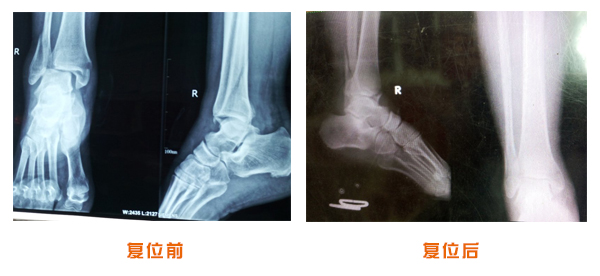

踝關節脫位骨折治療前后對比

尺橈骨克雷氏骨折治療前后